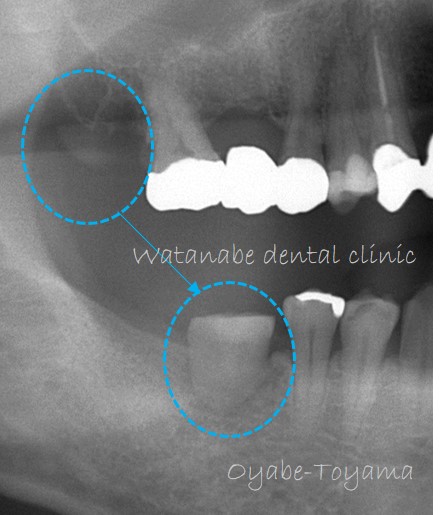

今回も親知らずの移植です。

オレンジ〇部分の歯が喪失しています。そして、青○が親知らずです。この親知らず(青○)と咬んでいる歯は無く、余っている状態です。このまま親知らずを残しておいても抜歯するしかありません。

このまま親知らずを抜歯してしまうのが勿体ないので、この親知らず(青○)をオレンジ○部分へ移植する計画としました。

下写真は移植直後の状態です。

移植した歯は歯の中の歯髄(血管、神経線維、細胞が入っている組織)が失活してしまうため、根管治療(歯髄が入っている組織を消毒すること)を行い、冠を被せていきます。

冠を被せた状態です(下写真)。これで、咬めるようになりました。

今のところ良好に経過しています。